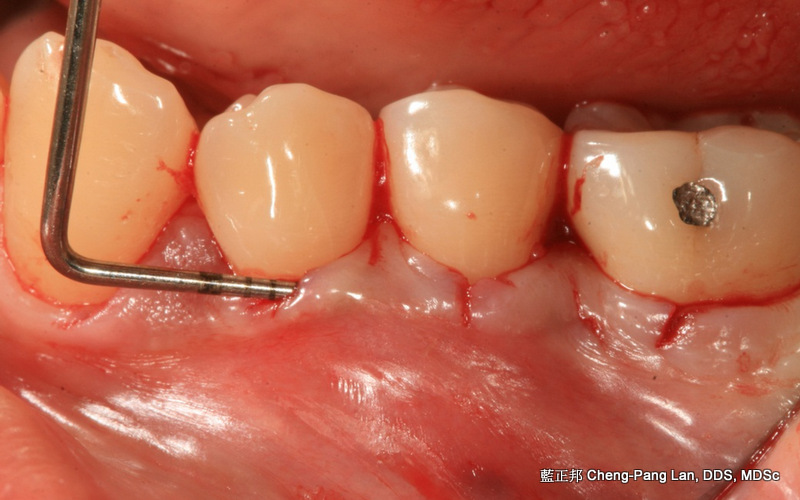

My first case of root coverage in 2008

Recipient Site: Harris’s technique, 1992